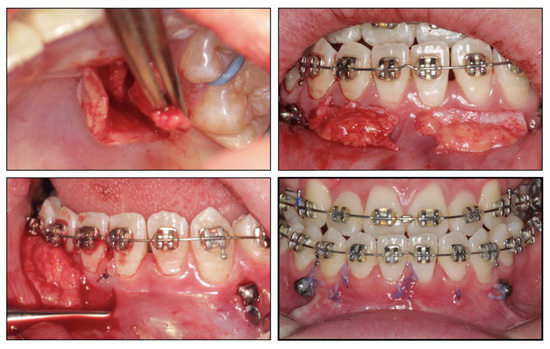

Figure 5. Subepithelial connective tissue transplantation.

2.4. Treatment Progress

Before the orthodontic treatment, the extraction of all retained deciduous teeth and maxillary first premolars were scheduled. After the extraction, both arches were bonded with preadjusted brackets (0.022-inch slot; 3M Unitek, Monrovia, CA, USA), aligned with initial 0.014-inch nickel titanium arch wires, and changed sequentially to eliminate crowding and provide leveling. Meanwhile, two impacted maxillary permanent canines were tracted through two auxiliary segmental 0.019 × 0.025-inch stainless steel arch wires with vertical helical loops (Figure 4). After 12 months, the canines were basically tracted into the right place. Presurgical decompensation started to increase the magnitude of surgical movement. The unfavorable tooth inclinations were corrected with 0.019 × 0.025-inch stainless steel arch wires through sliding mechanics to increase reverse overjet. A subepithelial connective tissue graft was also performed. Two connective tissue grafts were harvested from the palate and positioned in the prepared recipient site corresponding to the mandibular anterior region. The attached gingiva and keratinized tissue were augmented after the mucogingival surgery (Figure 5). After 34 months, the dentition preparation phase of presurgical treatment was completed in both arches (Figure 6).

Dental decompensation during presurgical orthodontic treatment is aimed to correct the torque of anterior teeth [15]. It is vital to keep an eye on the periodontal condition because mandibular anterior teeth always express crown lingual torque in skeletal class III malocclusion, which enhances the risks of gingival recession, fenestrations, and dehiscence [16]. Mucogingival surgery is a widely used technique to obtain attached gingiva, including free gingival graft, laterally positioned flap, and subepithelial connective tissue graft [17]. According to the thin periodontal biotype, we chose to use a subepithelial connective tissue graft, which was the best way to convert a thin, soft tissue to a thick biotype. Occlusal trauma caused by anterior crossbite was relieved by acquiring proper anterior overjet [18]. The outcome displayed that the keratinized and attached gingiva gained sufficient thickness, which preserved healthy a periodontal state and better represented the pink-white esthetic.